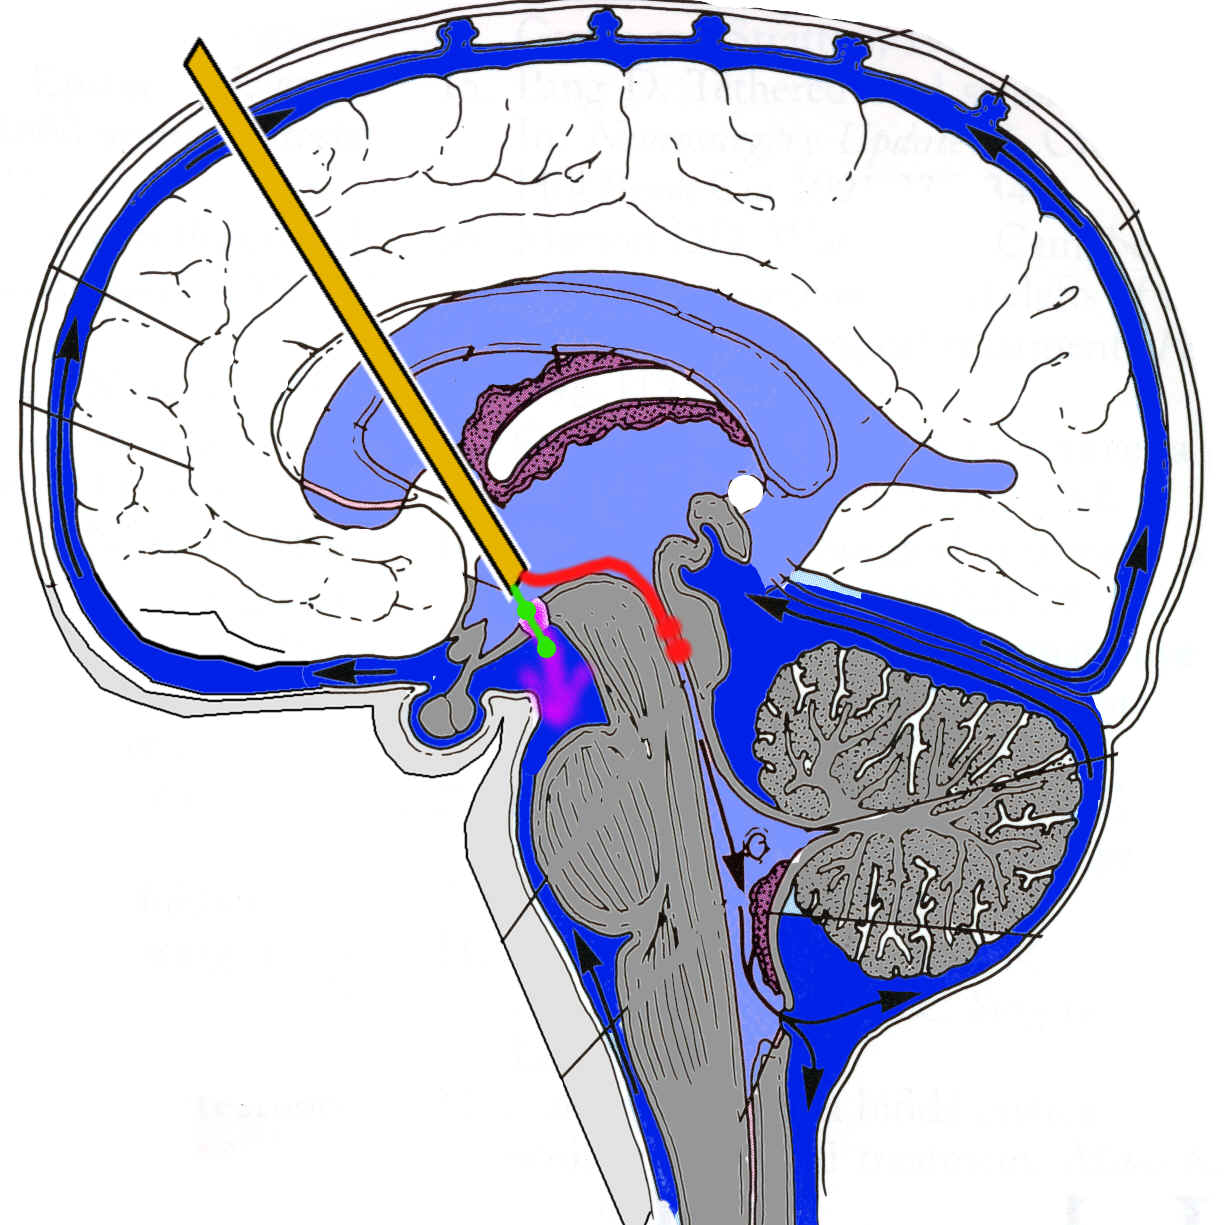

Die Abbildung zeigt als Schema alle bekannten Möglichkeiten auf endoskopischem Weg eine Aquäduktstenose zu therapieren: Mit dem Endoskop (gelb dargestellt) wird unter Ultraschall- und Neuronavigationssteuerung über den Seitenventrikel und das For.Monroi in den III. Ventrikel vorgegangen. Es gibt nun zwei verschiedene Möglichkeit der Therapie:

Ventrikulo-Zisternostomie ( = III. Ventrikulostomie):

Statt dass der Liquor wie normal vom III. Ventrikel über den Aquädukt in den IV. Ventrikel fließt, umgeht man das Hindernis, indem der Liquor von den inneren Liquorräumen (hellblau) durch ein künstlich geschaffenes Loch im Boden des III. Ventrikels direkt in die äußeren Liquorräume (dunkelblau) fließen kann. Hierzu wird unter endoskopischer Sicht ein bestimmter Ort am Boden des III. Ventrikels aufgesucht und dort ein Loch in diesen gemacht (grünes Instrument, Liquorfluß dann entsprechend des lila Pfeils). Um diese Operation durchzuführen, müssen verschiedene anatomische Voraussetzungen gegeben sein, die nur individuell beurteilt werden können. Die Ventrikulo-Zisternostomie kann als das Standardverfahren der endoskopischen Therapie der Aquäduktstenose angesehen werden.

Aquäduktoplastie:

Dieses Verfahren klingt auf den ersten Blick sehr logisch: Die Engstelle im Aquädukt wird mit einem (rot dargestellten) Instrument aufgedehnt und damit die Aquäduktstenose beseitigt. Dies ist aber nur möglich, wenn die Engstelle örtlich sehr umschrieben ist. Auch darf die Enge nicht so ausgeprägt sein, dass man sie nicht mit dem Instrument, das man zum Aufdehnen verwenden möchte, passieren kann. Bisher wird dieses Verfahren nur sehr selten angewandt. Die Erfahrungen damit sind also noch sehr begrenzt. Die bisherigen Erfahrungen lassen kaum eine kritische Wertung zu: bisher scheint es aber, dass die Komplikationsrate bei der Aquäduktoplastie höher zu sein scheint, als bei der klassischen III.Ventrikulostomie. Mit der Weiterentwicklung insbesondere flexibler Endoskope könnte dieses Verfahren in Zukunft möglicherweise an Bedeutung gewinnen.